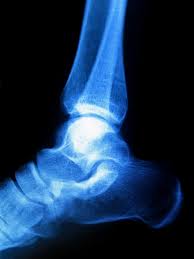

Haglund Deformity - : Radiographic evaluation of haglund's deformity.

Haglund Deformity - : Radiographic evaluation of haglund's deformity.. Haglund's deformity is a condition where there is a prominent posterosuperior aspect of the calcaneus. Haglund's deformity is where bone grows on the heel bone (calcaneus). It also referred to as haglund's disease (but it isn't really a disease). This condition is often precipitated by wearing shoes with rigid backs that rub against the heel. The soft tissue near the achilles tendon becomes irritated when the bony enlargement rubs against.

Patients with a haglund's deformity may or may not have pain. There is a noticeable swelling on the back of heel also called bump. Haglund's syndrome is a group of symptoms: Haglund deformity, also known as a pump bump, bauer bump, or mulholland deformity, is defined as bony enlargement formed at the posterosuperior aspect of the calcaneum. Haglund's deformity is where bone grows on the heel bone (calcaneus). Haglund's deformity is a bony enlargement of the back of the heel bone. Are you currently living with haglund's deformity? Haglund's deformity was described for the first time in 1928. With haglund's deformity, friction over the back of the heel causes the formation of bone spurs on the heel as the body lays down extra layers of bone to try and protect itself. Foot is an important body part. An enlargement of the bony section of your heel triggers this condition. It refers to the mechanical irritation between the posterior section of the calcaneus (heel bone) and the achilles tendon. 1 an isolated haglund's deformity can lead to posterior heel pain in runners due to adjacent soft traditional radiographic parameters one would use to measure haglund's deformity on plain films.